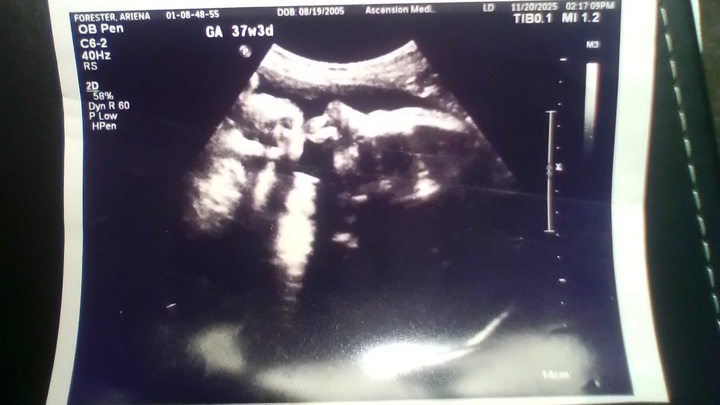

I am currently getting evicted by my landlord, and am due any day now with my baby. I have exhausted my options and unfortunately have not had any luck. I am hoping to get this camper to be able to have a place to live, instead of the huge possibility of being homeless. If anyone could help, I would really appreciate it. The goal is based off what the website says a down payment would be, plus some payments. Thank you to anyone who shares or donates.